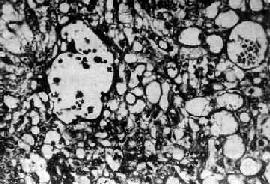

肉眼观,肿多为单侧性,以右侧为多,一般体积较大,平均直径为15~25cm,圆或卵圆形,表面光滑。切面多为实性,质较脆,灰白或粉白色,常有出血坏死及囊性变。镜检,组织形态较复杂及特殊,主要特征有下列几点:①网状结构,是最常见的形态,由星芒状的细胞形成疏松网状结构(图13-23),其中有微型小囊或间隙,囊腔被覆扁平或立方细胞,这种结构类似胚外中胚层结构;②内胚窦样结构,立方或柱状的细胞成单层排列,包绕毛细血管,形成一血管套样结构,这种结构横切面很像肾小球,称为Schiller-Duval小体,这种小体和大鼠胎盘内的Duval内胚窦结构相似,这种结构可能是由卵黄囊衍生演变而来;③多泡性卵黄囊样结构,特征是由扁平上皮、立方或低柱状的细胞形成大小不等的囊腔,其间隔以致密的结缔组织或疏松的粘液样间质,这种结构与胚胎时期的卵黄囊(胚外内胚层)相似;④在细胞内及细胞间隙可见PAS阳性的大小不等的嗜酸性小滴,免疫组化显示这种小滴含有甲胎蛋白(AFP),正常情况下,卵黄囊可合成AFP;⑤可见腺样、乳头状及实体细胞团结构等。

图13-23 内胚窦

呈疏松网状粘液样结构,其中有互相沟通、衬以上皮的腔隙及小囊腔,在细胞内外可见嗜酸性玻璃样小球及基底膜样物